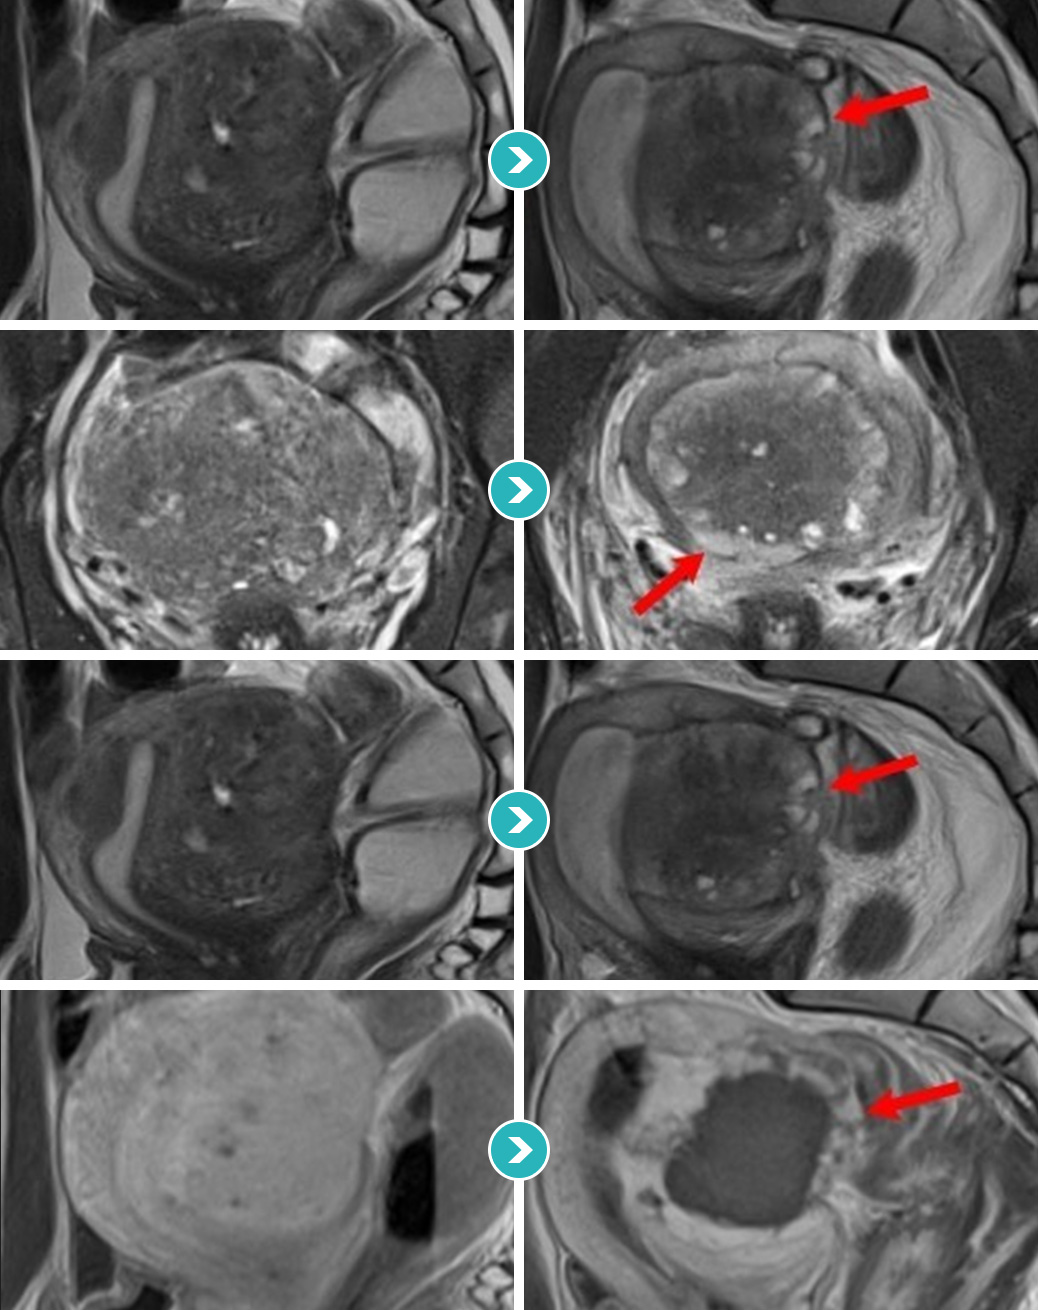

자궁선근증을 4가지 형태(경화형, 결절형, 낭종형, 분산형)로 분류할 수 있으며

각 유형의 맞춤 차별적 시술을 진행합니다.

자궁선근증은 환자에 따라 다양한 크기와 유형을 보이기 때문에 하이푸 시술 전에

정확한 치료플랜과 주변 조직에 영향을 주지 않는 정밀한 시술법이 요구됩니다.

자궁내막과 주변 조직을 보존하면서 초음파 집속 시술로

정밀하게 병변의 세포단위로 조사 ∙ 소멸시킵니다.

절개와 출혈없이 자궁근종선근증조직만을 세밀하게 선별 괴사시켜

치료의 완성도를 높입니다.